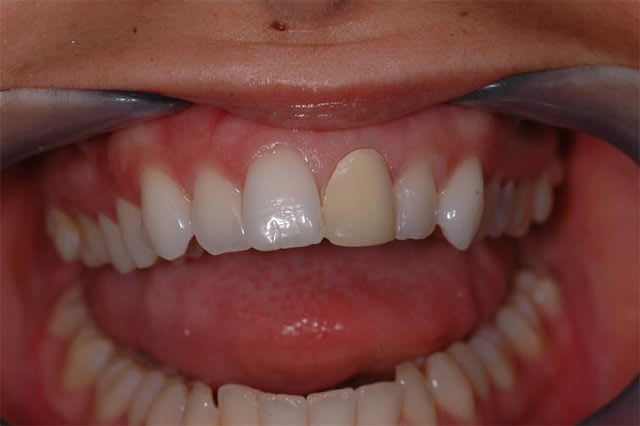

j'ai pas fait les bras à cette petite, mais je lui ai fait sa facette.

donc voici en presque en direct live le cas terminé...

facette feldspatique. vu l'épaisseur on a droit à une seule cuisson, donc faut pas se rater sur la teinte ou la forme.

teinte = OM2 teintier vita 3D master ! c'est dire si elle a les dents blanches la demoiselle. au départ de cas, je pensais qu'on était sur un A2, mais voila ce que donne la provisoire qui contrairement aux apparences était bien en A2.